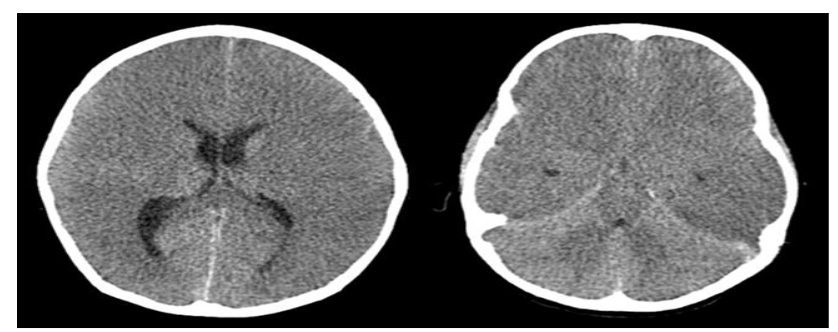

AFCE and AEM/HSES represent severe end of the spectrum of ITES, characterised by life threatening hyperacute onset of cerebral oedema or multi-organ dysfunction respectively. They carry a high mortality rate of about 80%. Both the entities have similar clinical presentations and radiological findings and probably are a part of the same severe neuro-inflammatory process.

AFCE and AEM/HSES represent severe end of the spectrum of ITES, characterised by life-threatening hyperacute onset of cerebral oedema or multi-organ dysfunction respectively. They carry a high mortality rate of about 80%. Both the entities have similar clinical presentations and radiological findings and probably are a part of the same severe neuro-inflammatory process.

FIG 8 (A–B) Axial CT scan in a 7-year-old with AFCE showing diffuse cerebral edema (A) with ‘white’ cerebellum sign (reversal) (B) – prognosis is very poor in this case (Image courtesy – Dr Nihal Reddy, Consultant Neuro-radiologist, Hyderabad)